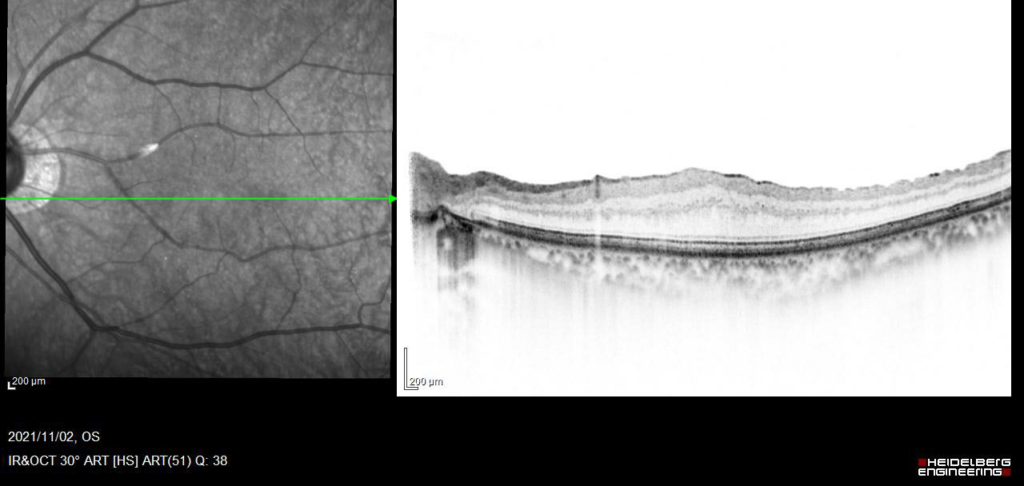

黄斑耳側の網膜表面に膜組織による高反射がみられ、血管が蛇行し偏位がみられる。

ERMを示す高反射が網膜前面にみられ、皺壁を形成している。黄斑網膜は肥厚し、中心窩は外顆粒層の挙上により三角形に隆起している。